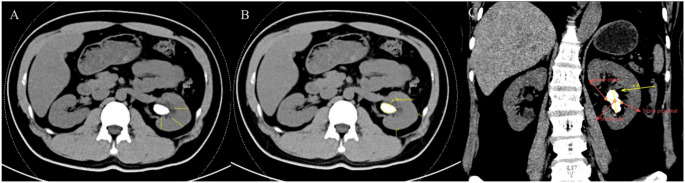

本研究旨在确定接受经皮肾镜取石术(PCNL)的代谢综合征(MetS)患者发生全身性炎症反应综合征(SIRS)的术前危险因素,并建立个体化风险分层的预测nomogram。对2021年1月至2024年12月期间接受PCNL的245例MetS患者进行了回顾性分析,其中27.8%的患者发生了术后SIRS。患者按7:3的比例随机分配到训练组和验证组。最小绝对收缩和选择算子(LASSO)回归最初用于选择候选预测因子,然后进行单变量和多变量逻辑回归分析以确定独立风险因素。随后,基于显著变量构建了nomogram,并使用受试者工作特征(ROC)曲线、校准图和决策曲线分析(DCA)进行评估。多因素分析确定了术后SIRS的五个独立预测因素:结石密度的较高标准差、肾实质厚度的减少、肾外侧和后周脂肪厚度的增加以及鹿角结石的存在

This study aimed to identify preoperative risk factors for systemic inflammatory response syndrome (SIRS) in patients with metabolic syndrome (MetS) undergoing percutaneous nephrolithotomy (PCNL) and to develop a predictive nomogram for individualized risk stratification. A retrospective analysis was conducted on 245 MetS patients who underwent PCNL between January 2021 and December 2024, among whom 27.8% developed postoperative SIRS. Patients were randomly assigned to training and validation cohorts in a 7:3 ratio. Least absolute shrinkage and selection operator (LASSO) regression was initially applied to select candidate predictors, followed by univariate and multivariate logistic regression analyses to identify independent risk factors. A nomogram was subsequently constructed based on the significant variables and evaluated using receiver operating characteristic (ROC) curves, calibration plots, and decision curve analysis (DCA). Multivariate analysis identified five independent predictors of postoperative SIRS: higher standard deviation of stone density, reduced renal parenchymal thickness, increased lateral and posterior perirenal fat thicknesses, and the presence of staghorn calculi (P < 0.05). The nomogram demonstrated good discriminative ability, with an area under the ROC curve (AUC) of 0.888 (95% CI: 0.834-0.942) in the training cohort and 0.882 (95% CI: 0.802-0.962) in the validation cohort. The calibration curve and the Hosmer-Lemeshow test (P = 0.1485) indicated good model calibration and fit. DCA further confirmed the clinical utility of the model. This nomogram offers a reliable preoperative tool for SIRS risk stratification in MetS patients undergoing PCNL, aiding early intervention and personalized perioperative management.